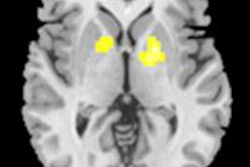

CHICAGO - Researchers employing functional MRI have found that children with attention deficit/hyperactivity disorder (ADHD) may show different brain activity patterns when processing visual attention information.

At a press briefing at the RSNA 2011 meeting, Xiaobo Li, PhD, assistant professor of radiology at the Albert Einstein College of Medicine, said the study among 18 children with ADHD and 18 controls indicated that "the pattern of brain activity for processing visual attention information looks a little different in children with ADHD."

"The findings are supported by existing research that shows an increased involvement of the anterior cingulate cortex and disrupted frontoparietal connections during the visual attention processing pathway in ADHD," she said.

"Our study also suggests that bilateral middle temporal gyri may be associated with the psychopathology of ADHD," she added.

The research team performed functional MRI scans to capture brain activity in the 9- to 15-year-olds diagnosed with ADHD, comparing the results to those in children without the diagnosis. The test requires the children to pay attention, visualize, remember, and compare numbers flashed on a screen while being scanned, Li explained.